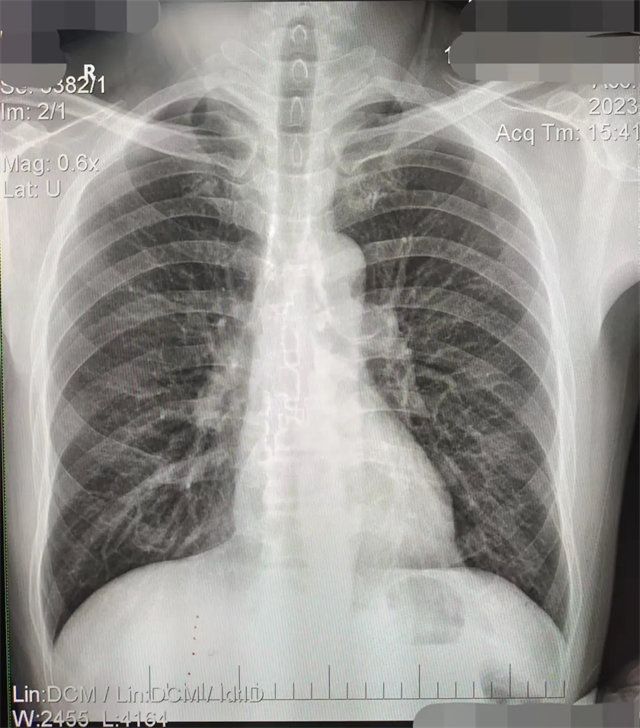

拍攝的不合格胸片的缺陷和解決方法

缺陷:兩肩胛骨未拉開肺野之外,吸氣不完全,且存在金屬飾品遮擋。

解決:去除金屬飾品及內(nèi)衣后重新按標(biāo)準(zhǔn)體位攝片即可。